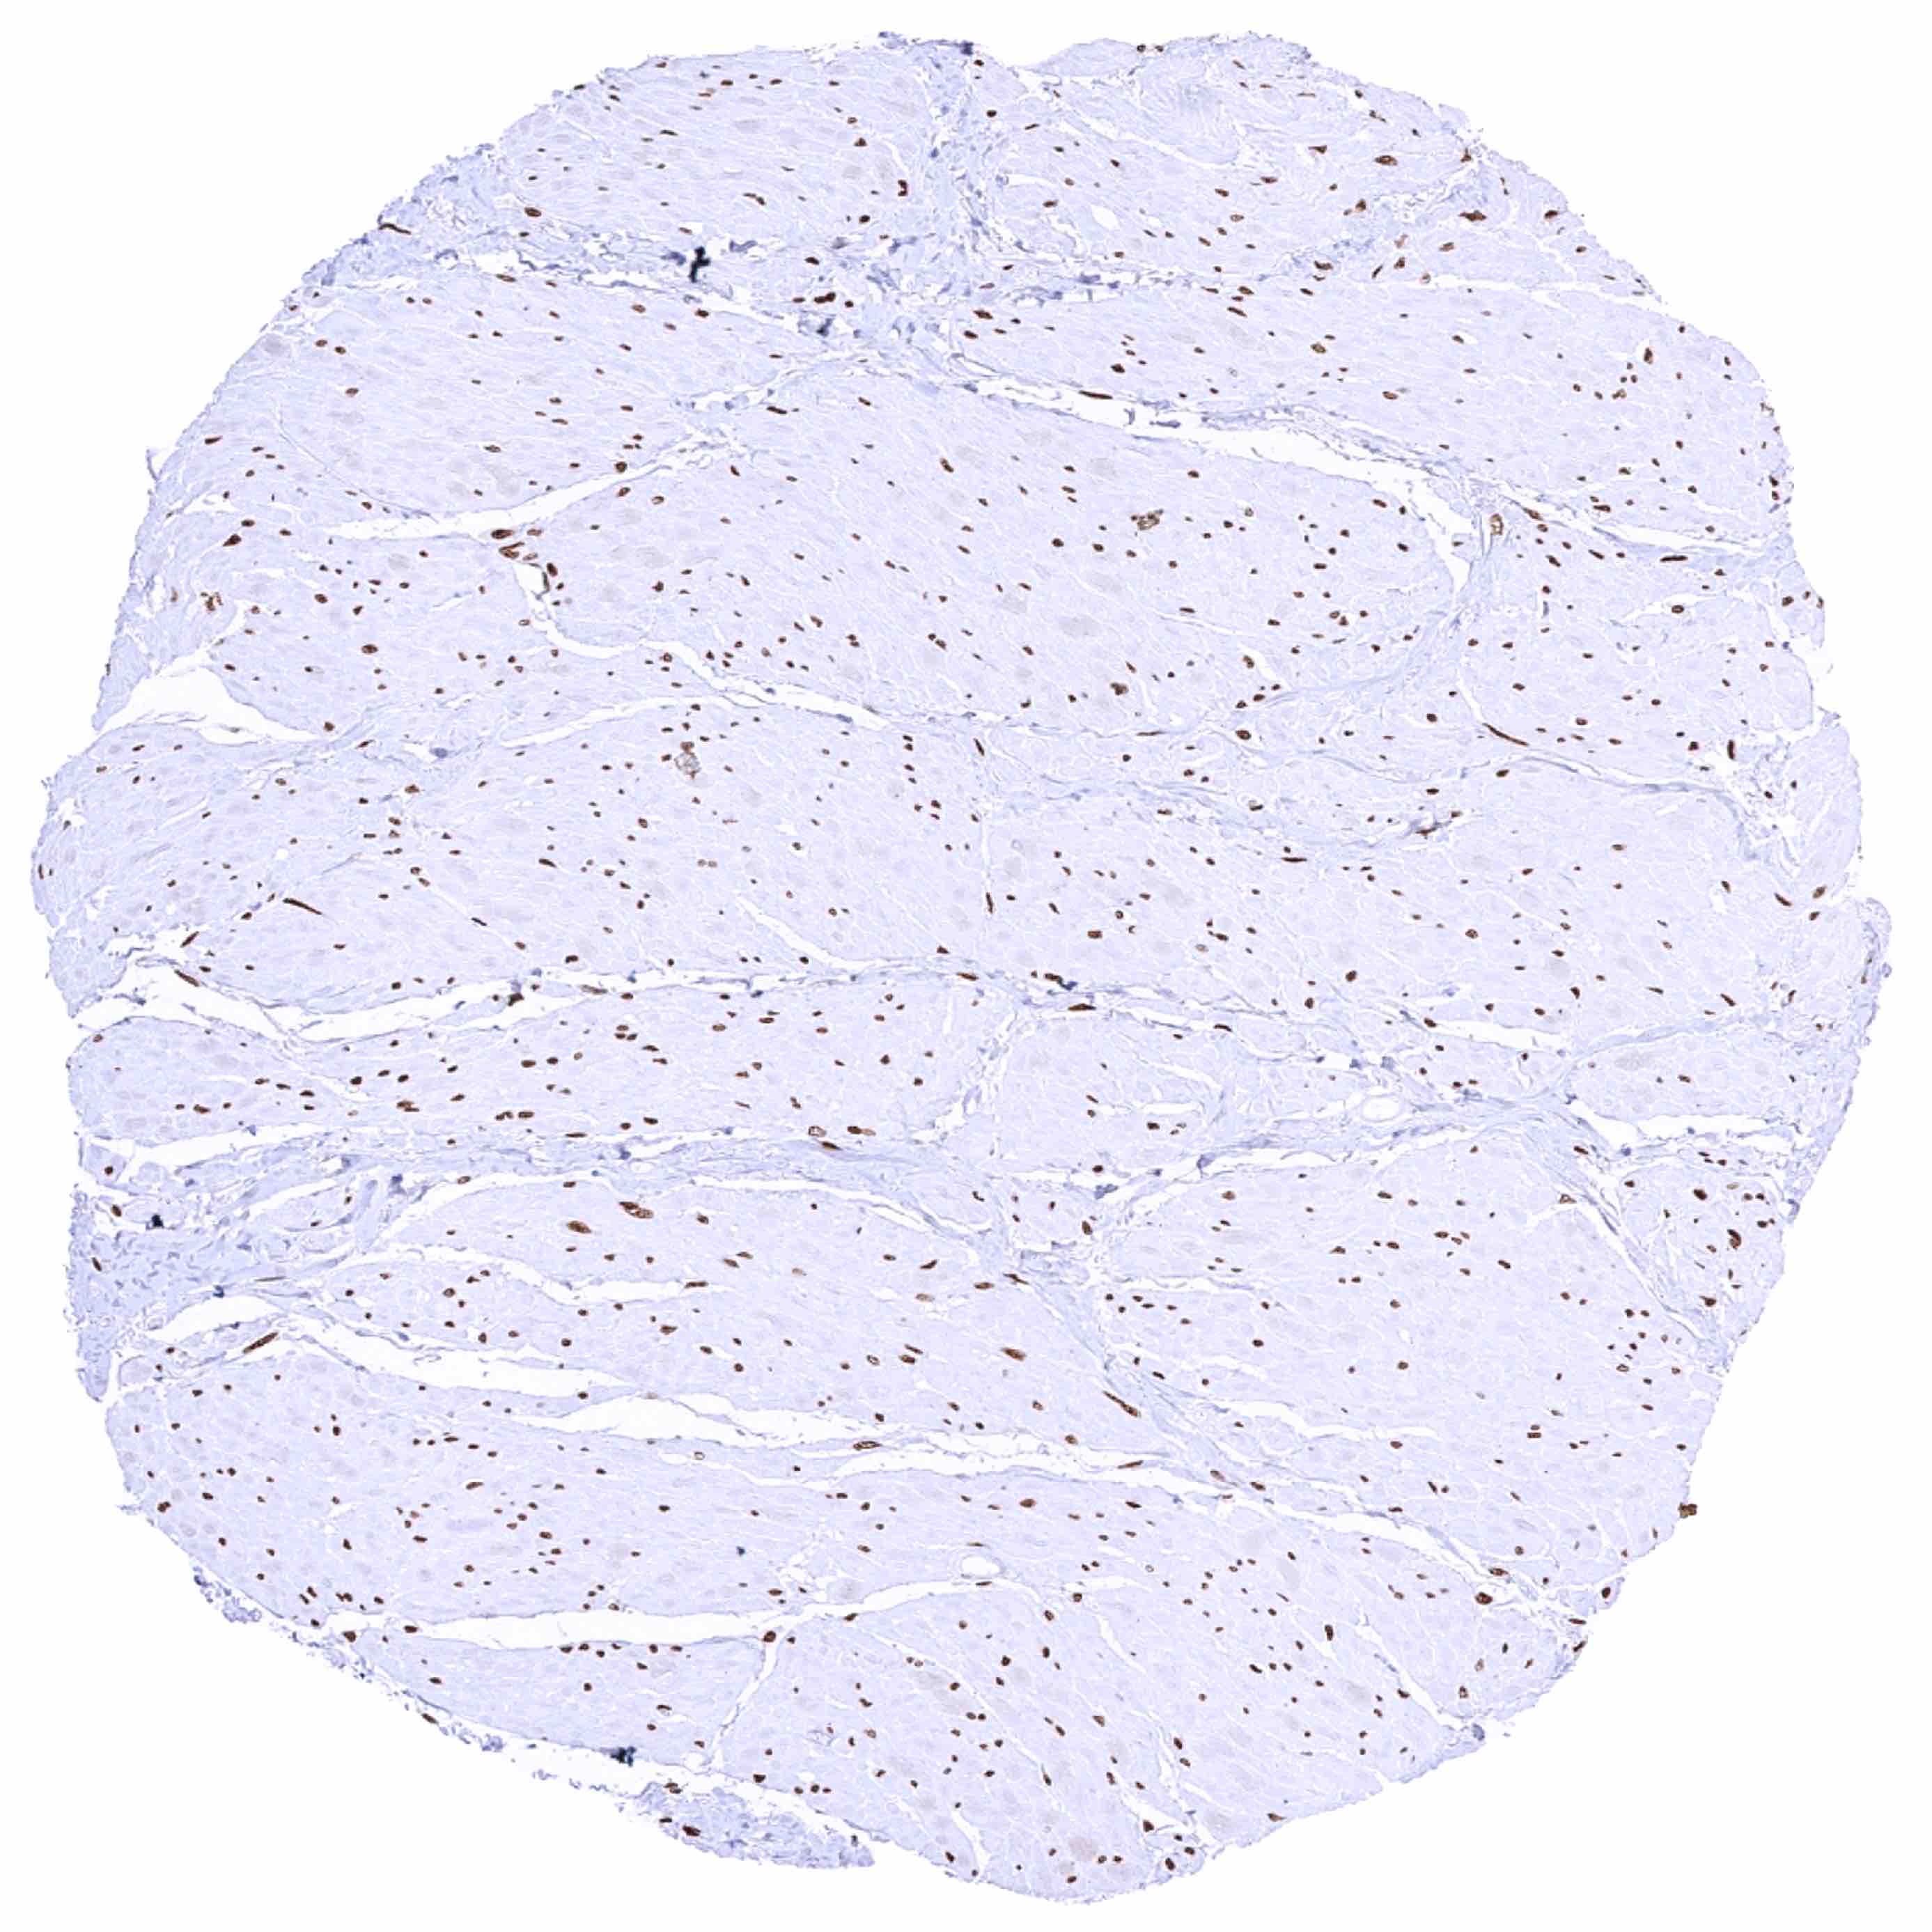

Heart muscle